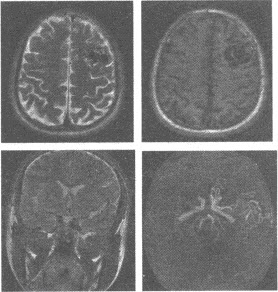

C:CT及MRI上可见液-液平面

D:病灶主要由大小不等海绵状血池组成,分为原发性和继发性两种